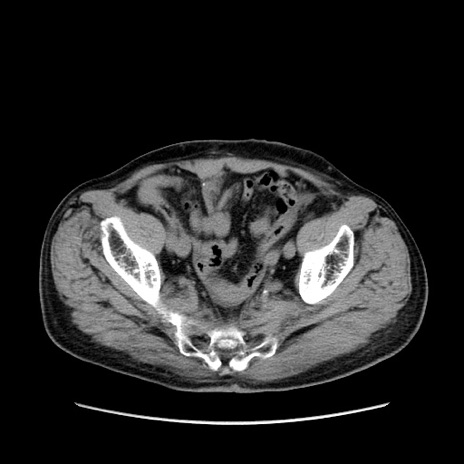

症例24(横断像)

【症例】80歳代男性

【主訴】左側腹部痛、嘔吐

【現病歴】本日早朝より左腹部に痛みあり。昼頃嘔吐認めたため、救急要請。

【既往歴】直腸癌(Mile手術)、胆摘

【身体所見】意識清明、BT 35.9℃、BP 221/93mmHg、SpO2 97%(RA) 、腹部:左ストーマ周囲に限局性の腹部膨隆あり。 膨隆部自発痛・圧痛あり・軟。

【データ】WBC 7700、CRP 0.09